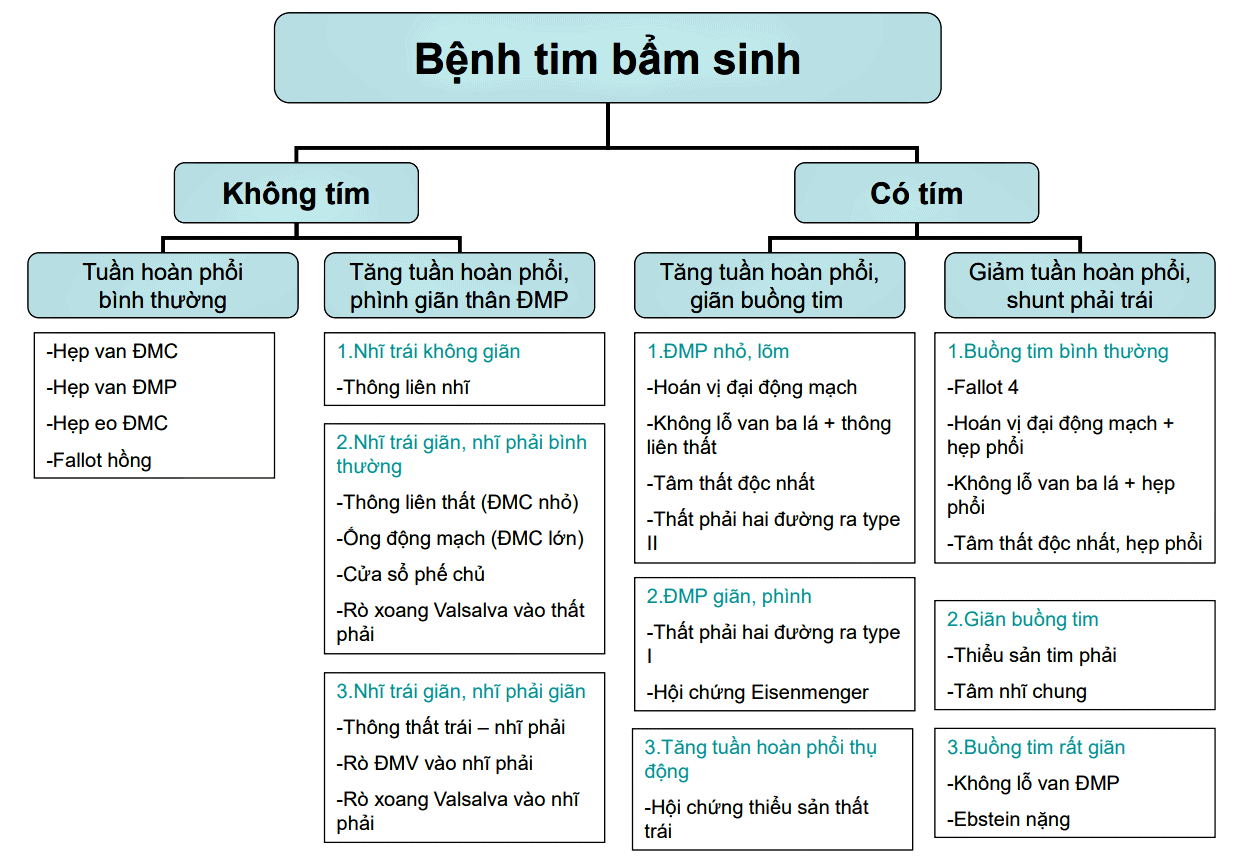

* Phân loại – Tư thế chụp thẳng sau trước (PA): chỉ thấy các bờ phía ngoài của tim – Tư thế chụp nghiêng: * Tư thế thẳng * Tư thế nghiêng – Thông liên thất (Ventricular septal defect – VSD) là một khiếm khuyết của vách liên thất, tức là vách ngăn giữa hai buồng tâm thất của tim. Vách liên thất là một cấu trúc phức tạp gồm: phần cơ, phần màng, phần phễu, phần buồng nhận. – Nguyên nhân: hiện chưa rõ, tuy nhiên ncó đề cập tới 1 số yếu tố như do di truyền hay gia đình: cha mẹ hay anh, chị em mắc bệnh tim bẩm sinh trong đó có bệnh TLT thì có nguy cơ mắc bệnh cao hơn. Tương tự ở – Sinh lý bệnh: – Phân loại: * Chẩn đoán X-Quang – Hội chứng Eisenmenger: trường hợp Shunt (T) => (P) lâu ngày, dẫn đến tăng áp động mạch phổi làm đảo ngược Shunt (P) => (T), kèm tím tái: * Cắt lớp vi tính: – Thông liên nhĩ (Atrial Septal Defect – ASD) là một dạng bệnh tim bẩm sinh làm cho máu chảy giữa hai buồng nhĩ trái và nhĩ phải. Bình thường nhĩ trái và nhĩ phải tách biệt nhau bởi một vách được gọi là vách liên nhĩ. Nếu vách này bị khiếm khuyết hoặc không có, máu giàu oxy có thể chảy trực tiếp từ bên trái của tim để trộn với máu kém oxy ở bên phải của tim và ngược lại. Điều này có thể dẫn đến máu động mạch cung cấp cho não, các cơ quan và các mô có nồng độ oxy thấp hơn bình thường. – Phân loại: * Chẩn đoán X-quang => Case lâm sàng 1: * Chẩn đoán CT: thuốc cản quang chảy từ nhĩ trái sang nhĩ phải. * Hội chứng Eisenmenger – Còn ống động mạch (Patent ductus arteriosis – PDA) tình trạng ống động mạch (ống Botal) nối giữa động mạch chủ và động mạch phổi trong thời kỳ bào thai không bị tắc lại sau sinh (thông thường ống này sẽ hoàn toàn tắc lại trong vòng 2 tháng sau sinh), mà vẫn tiếp tục tồn tại và hoạt động kéo dài. * Hình ảnh X-quang * Chẩn đoán CT => Case lâm sàng 1: => Case lâm sàng 2: => Case lâm sàng 3: => Case lâm sàng 4: => Case lâm sàng 5: – Tứ chứng Fallot (Tetralogy of Fallot – 4F) là bệnh tim bẩm sinh tím thường gặp nhất với tỉ lệ 10% trẻ bị tim bẩm sinh. – Tứ chứng Fallot là bệnh lý tiến triển nặng theo thời gian. Tùy theo mức độ hẹp đường thoát thất phải và kích thước thông liên thất, triệu chứng tím thường xuất hiện trong giai đoạn nhũ nhi hoặc trẻ nhỏ. Trong những trường hợp nặng, tím xuất hiện ngay từ những ngày đầu sơ sinh. * Hình ảnh X-quang => Case lâm sàng 1: => Case lâm sàng 2: – Hẹp eo động mạch chủ (Coarctation of aorta – COA) thường hẹp sau chỗ xuất phát động mạch dưới đòn trái. Hậu quả, dòng máu trước chỗ hẹp bị cản trở, khiến áp lực buồng tim gia tăng, dẫn tới phì đại thất trái và suy tim. – Hình ảnh X-quang: => Case lâm sàng 1: => Case lâm sàng 2: => Case lâm sàng 3: => Case lâm sàng 4: => Case lâm sàng 5: * Giả hẹp eo động mạch chủ => Case lâm sàng 1: => Case lâm sàng 2: => Case lâm sàng 3: => Case lâm sàng 4: * Chẩn đoán CT => Case lâm sàng 1: => Case lâm sàng 2: => Case lâm sàng 3:II. Giải phẫu

III. Chẩn đoán hình ảnh

1. Thông liên thất

– Thông thường khi trẻ sinh ra, vách này không có lỗ thông vì vậy không cho phép máu của hai tâm thất hòa trộn với nhau. Trong vách liên thất là nơi có phần đầu quan trọng của hệ thống thần kinh dẫn truyền xung động từ nhĩ đến các phần cơ thất.

– Thông liên thất là bệnh tim bẩm sinh thường gặp nhất trong tất cả các bệnh tim bẩm sinh chiếm 15-20% tất cả các bệnh tim bẩm sinh, đó là chưa kể đến các thông liên thất trong các bệnh tim bẩm sinh có tím phức tạp.

+ Thông liên thất lỗ nhỏ (Bệnh Roger): Đường kính lỗ thông < 1/3 so lỗ van động mạch chủ (ĐMC) hay < 0,5cm2, luồng thông ít từ thất trái qua thất phải lên động mạch phổi (ĐMP) nên gây rối loạn huyết động học không đáng kể, chưa ảnh hưởng đến chức năng phổi và tim.

+ Thông liên thất lỗ vừa: còn gọi là TLT hạn chế, đường kính lỗ thông > 1/3 và < lỗ van ĐMC. Có rối loạn huyết động học đáng kể vì luồng shunt từ tâm thất trái sang tâm thất phải vào ĐMP, lên phổi làm tăng lưu lượng tuần hoàn lên phổi rồi về nhĩ trái xuống thất trái và tăng gánh tâm trương thất trái diễn tiến dẫn đến tăng áp động mạch phổi rồi dần dần ảnh hưởng thất phải.

+ Thông liên thất lỗ lớn: còn gọi là TLT không hạn chế, lỗ thông > lỗ van ĐMC. Vì lỗ thông lớn và luồng thông nhiều

nên gây rối loạn huyết động nặng nề với tặng tuần hoàn phổi, tăng gánh thể tích thất trái, tăng áp động mạch phổi và tăng gánh thất phải. Giai đoạn đầu áp lực thất trái cao hơn áp lực thất phải lúc đó luồng thông từ trái sang phải. Bệnh diễn tiến nhanh gây ảnh hưởng đến chức năng thất trái khi áp lực hệ phổi cao hơn hệ chủ gây đảo chiều shunt phải-trái tạo nên phức hợp Eisenmenger, tăng áp động mạch phổi cố định.

+ Thông liên thất quanh màng: 70-80%

+ Thông liên thất phần buồng nhận: 3-8%

+ Thông liên thất phần cơ bè: 5-20%

+ Thông liên thất phần thoát / phần phễu: 5-7%

– Tùy thuộc kích thướng lỗ thông hình ảnh X-quang rất khác nhau

+ Lỗ thông nhỏ: hình ảnh X-quang thường bình thường.

+ Lô thông vừa: shunt trái – phải => giãn nhĩ trái và thất trái do tăng gánh tâm trương. Có thể giãn cung động mạch phổi, tăng lưu lượng tuần hoàn phổi chủ động.

+ Lỗ thông lớn: thất phải có thể giãn do tăng gánh tâm thu. Tăng kích thước động mạch phổi, giảm tuần hoàn phổi ngoại biên.

+ Động mạch chủ bình thường hoặc nhỏ do giảm cung lượng tim.

+ Bóng tim to nhưng khi đảo shunt có khuynh hướng thu nhỏ lại gần bình thường, thất phải dày làm mỏm tim hơi tròn và vênh lên cao trên vòm hoành.

+ Giãn cung động mạch phổi và có thể thấy giãn 2 gốc động mạch phổi.

+ Rốn phổi tăng đậm trong khi đó phế trường ngoại vi sáng hơn bình thường tạo hình ảnh cắt cụt điển hình trong phức hợp Eisenmenger.2. Thông liên nhĩ

– Trong quá trình phát triển của thai, vách liên nhĩ phát triển để phân chia nhĩ trái và phải. Tuy nhiên, một lỗ ở vách được gọi là lỗ bầu dục cho phép máu từ nhĩ phải qua nhĩ trái trong quá trình phát triển của thai. Lỗ thông này cho phép máu không đi qua phổi thai không có chức năng, trong khi thai vẫn nhận oxy từ nhau. Một lớp mô được gọi là vách nguyên phát hoạt động như một van tại lỗ bầu dục trong quá trình phát triển thai. Sau khi sinh áp lực bên phải của tim giảm khi phổi mở và bắt đầu hoạt động, làm cho lỗ bầu dục đóng hoàn toàn.

– Thông liên nhĩ là bệnh lý tim bẩm sinh chiếm từ 7-15% và xếp hàng thứ 5 trong các bệnh lý tim bẩm sinh nói chung, bệnh chủ yếu gặp ở nữ giới.

+ Thông liên nhĩ lỗ tiên phát (ASD-op): có thể xảy ra đơn độc nhưng thông thường xảy ra trong bệnh cảnh tim bẩm sinh phức tạp (kênh nhĩ thất), vị trí nằm thấp, sát van nhĩ thất.

+ Thông liên nhĩ lỗ thứ phát (ASD-os): Đây là tình trạng thường gặp nhất, chiếm đến 70% các trường hợp, có thể xảy ra đơn độc và vị trí nằm ở trung tâm của vách liên nhĩ. Lỗ thông liên nhĩ thứ phát thường có kích thước từ 10-30 mm.

+ Thông liên nhĩ xoang tĩnh mạch (ASD-sv): Đây là một tình trạng hiếm gặp và có 2 loại: Loại tĩnh mạch chủ trên: nằm ngay dưới lỗ đổ của tĩnh mạch chủ trên vào nhĩ phải. Thông liên nhĩ xoang tĩnh mạch chủ trên thường đi kèm với hồi lưu tĩnh mạch phổi bất thường / Loại tĩnh mạch chủ dưới thì nằm sát lỗ đổ vào của tĩnh mạch chủ dưới vào nhĩ phải.

+ Thông liên nhĩ xoang vành (ASD-cs): do mất trần xoang vành, trường hợp này vô cùng hiếm gặp.

– Khoảng 15% các trường hợp bóng tim bình thường.

– Luồng thông trái => phải: bóng tim to do giãn nhĩ phải và thất phải, mỏm tim chếch lên. Nhĩ trái và thất trái bình thường.

– Động mạch chủ bình thường hoặc nhỏ hơn do giảm cung lượng tim.

– Cung động mạch phổi giãn do tăng cung lượng => tăng lưu lượng tuần hoàn phổi chủ động.

– Khi tăng áp lực động mạch phổi nặng => đảo chiều luồng thông => động mạch phổi giãn ở trung tâm và co nhỏ ở ngoại vi => phế trường ngoại vi sáng hơn bình thường.

– Hình ảnh đảo ngược shunt có thể được xác định nếu nhìn thấy thuốc cản quang chảy từ bên phải của trái tim sang bên trái.3. Còn ống động mạch

– Ống động mạch nối liền nơi phân nhánh động mạch phổi và eo động mạch chủ, dưới chỗ xuất phát động mạch dưới đòn. Ống động mạch thông thương trong thời kỳ bào thai và đóng lại ngay sau sinh do tác dụng của sự sụt giảm Prostaglandin E2 và tăng nồng độ O2 máu nhờ động tác thở.

– Còn ống động mạch xảy ra trong 5-10% tất cả các bệnh tim bẩm sinh, thường gặp ở nữ hơn nam (nam/nữ = 1/3).

+ Quai động mạch chủ thường lớn do tăng cung lượng tim.4. Tứ chứng Fallot

– Bao gồm 4 tổn thương:

+ Thông liên thất: quanh màng, cơ bè

+ Động mạch chủ lệch phải cưỡi ngựa trên vách liên thất

+ Hẹp đường thoát thất phải (hẹp động mạch phổi): hẹp van, hẹp phễu, không lỗ van, không van, hep nhánh xa động mạch phổi.

+ Dày thất phải.

+ Phối hợp: cung động mạch chủ bên phải (25%), còn ống động mạch (2%), bất thường động mạch vành.

– Sinh lý bệnh:

+ Tăng gánh áp lực thất phải: dày thất phải => xơ hóa thất phải => suy tim phải.

+ Shunt phải => trái: tím nặng khi khóc hoặc gắng sức.

– Bóng tim thường không lớn, đôi lúc nhỏ hơn bình thường

– Khuyết cung động mạch phổi (do hẹp động mach)

– Tim hình chiếc giầy (Boot-shaped): thất phải phì đại, mỏm tim chếch lên.

– Tuần hoàn phổi giảm: các động mạch phổi nhỏ => phế trường sáng.

– Quai động mạch chủ thường nằm bên phải (25%)5. Hẹp eo ĐM chủ

– Hẹp eo động mạch chủ trẻ em thường nằm trước vị trí ống động mạch, còn người lớn thường nằm sau ống động mạch

– Chiếm 5-8% của tất cả các dị tật tim bẩm sinh.

– Thường gặp hơn ở nam giới, tỷ lệ nam:nữ = ~ 2-3: 1